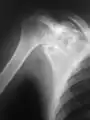

A variety of imaging studies can be used to diagnose chondroblastoma, with radiographs being the most common.[10][8] Laboratory studies are not considered useful.[14] Classical chondroblastoma (appearing on long bones) appears as a well-defined eccentric oval or round lytic lesion that usually involves the adjacent bone cortex without periosteal reaction.[10][13] A sclerotic margin can be seen in some cases.[10][13] For long bone chondroblastomas the tumor is typically contained to the epiphysis or apophysis but may extend through the epiphyseal plate.[10][13] Chondroblastomas are usually located in the medullary portion of bones and can, in some cases, include the metaphysis.[10][13] However, true metaphyseal chondroblastomas are rare and are typically the result of an extension from a neighboring epiphyseal legion.[10][13] Most lesions are less than 4 cm.[10] A mottled appearance on the radiograph is not atypical and indicates areas of calcification which is commonly associated with skeletally immature patients.[10] Additionally, one-third of all cases involve aneurysmal bone cysts which are thought to be the result of stress, trauma or hemorrhage.[10] In cases involving older patients or flat bones, typical radiographic presentation is not as common and may mimic aggressive processes.[10][13]

1. a. X-ray of chondroblastoma of thigh bone near knee

2. X-ray of chondroblastoma of shoulder blade